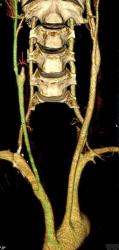

Мужчина, 62 года. Перенес ишемический инсульт в бассейне правой средней мозговой артерии.

На КТ-ангиографии выявлена окклюзия правой внутренней сонной артерии в области развилки в виде паламени свечи (красная стрелка), стеноз высокой степени в устье правой вертебральной артерии (желтая стрелка), небольшой перегиб в устье левой вертебральной артерии (голубая стрелка).

Больному успешно установлен стент в устье правой вертебральной артерии.